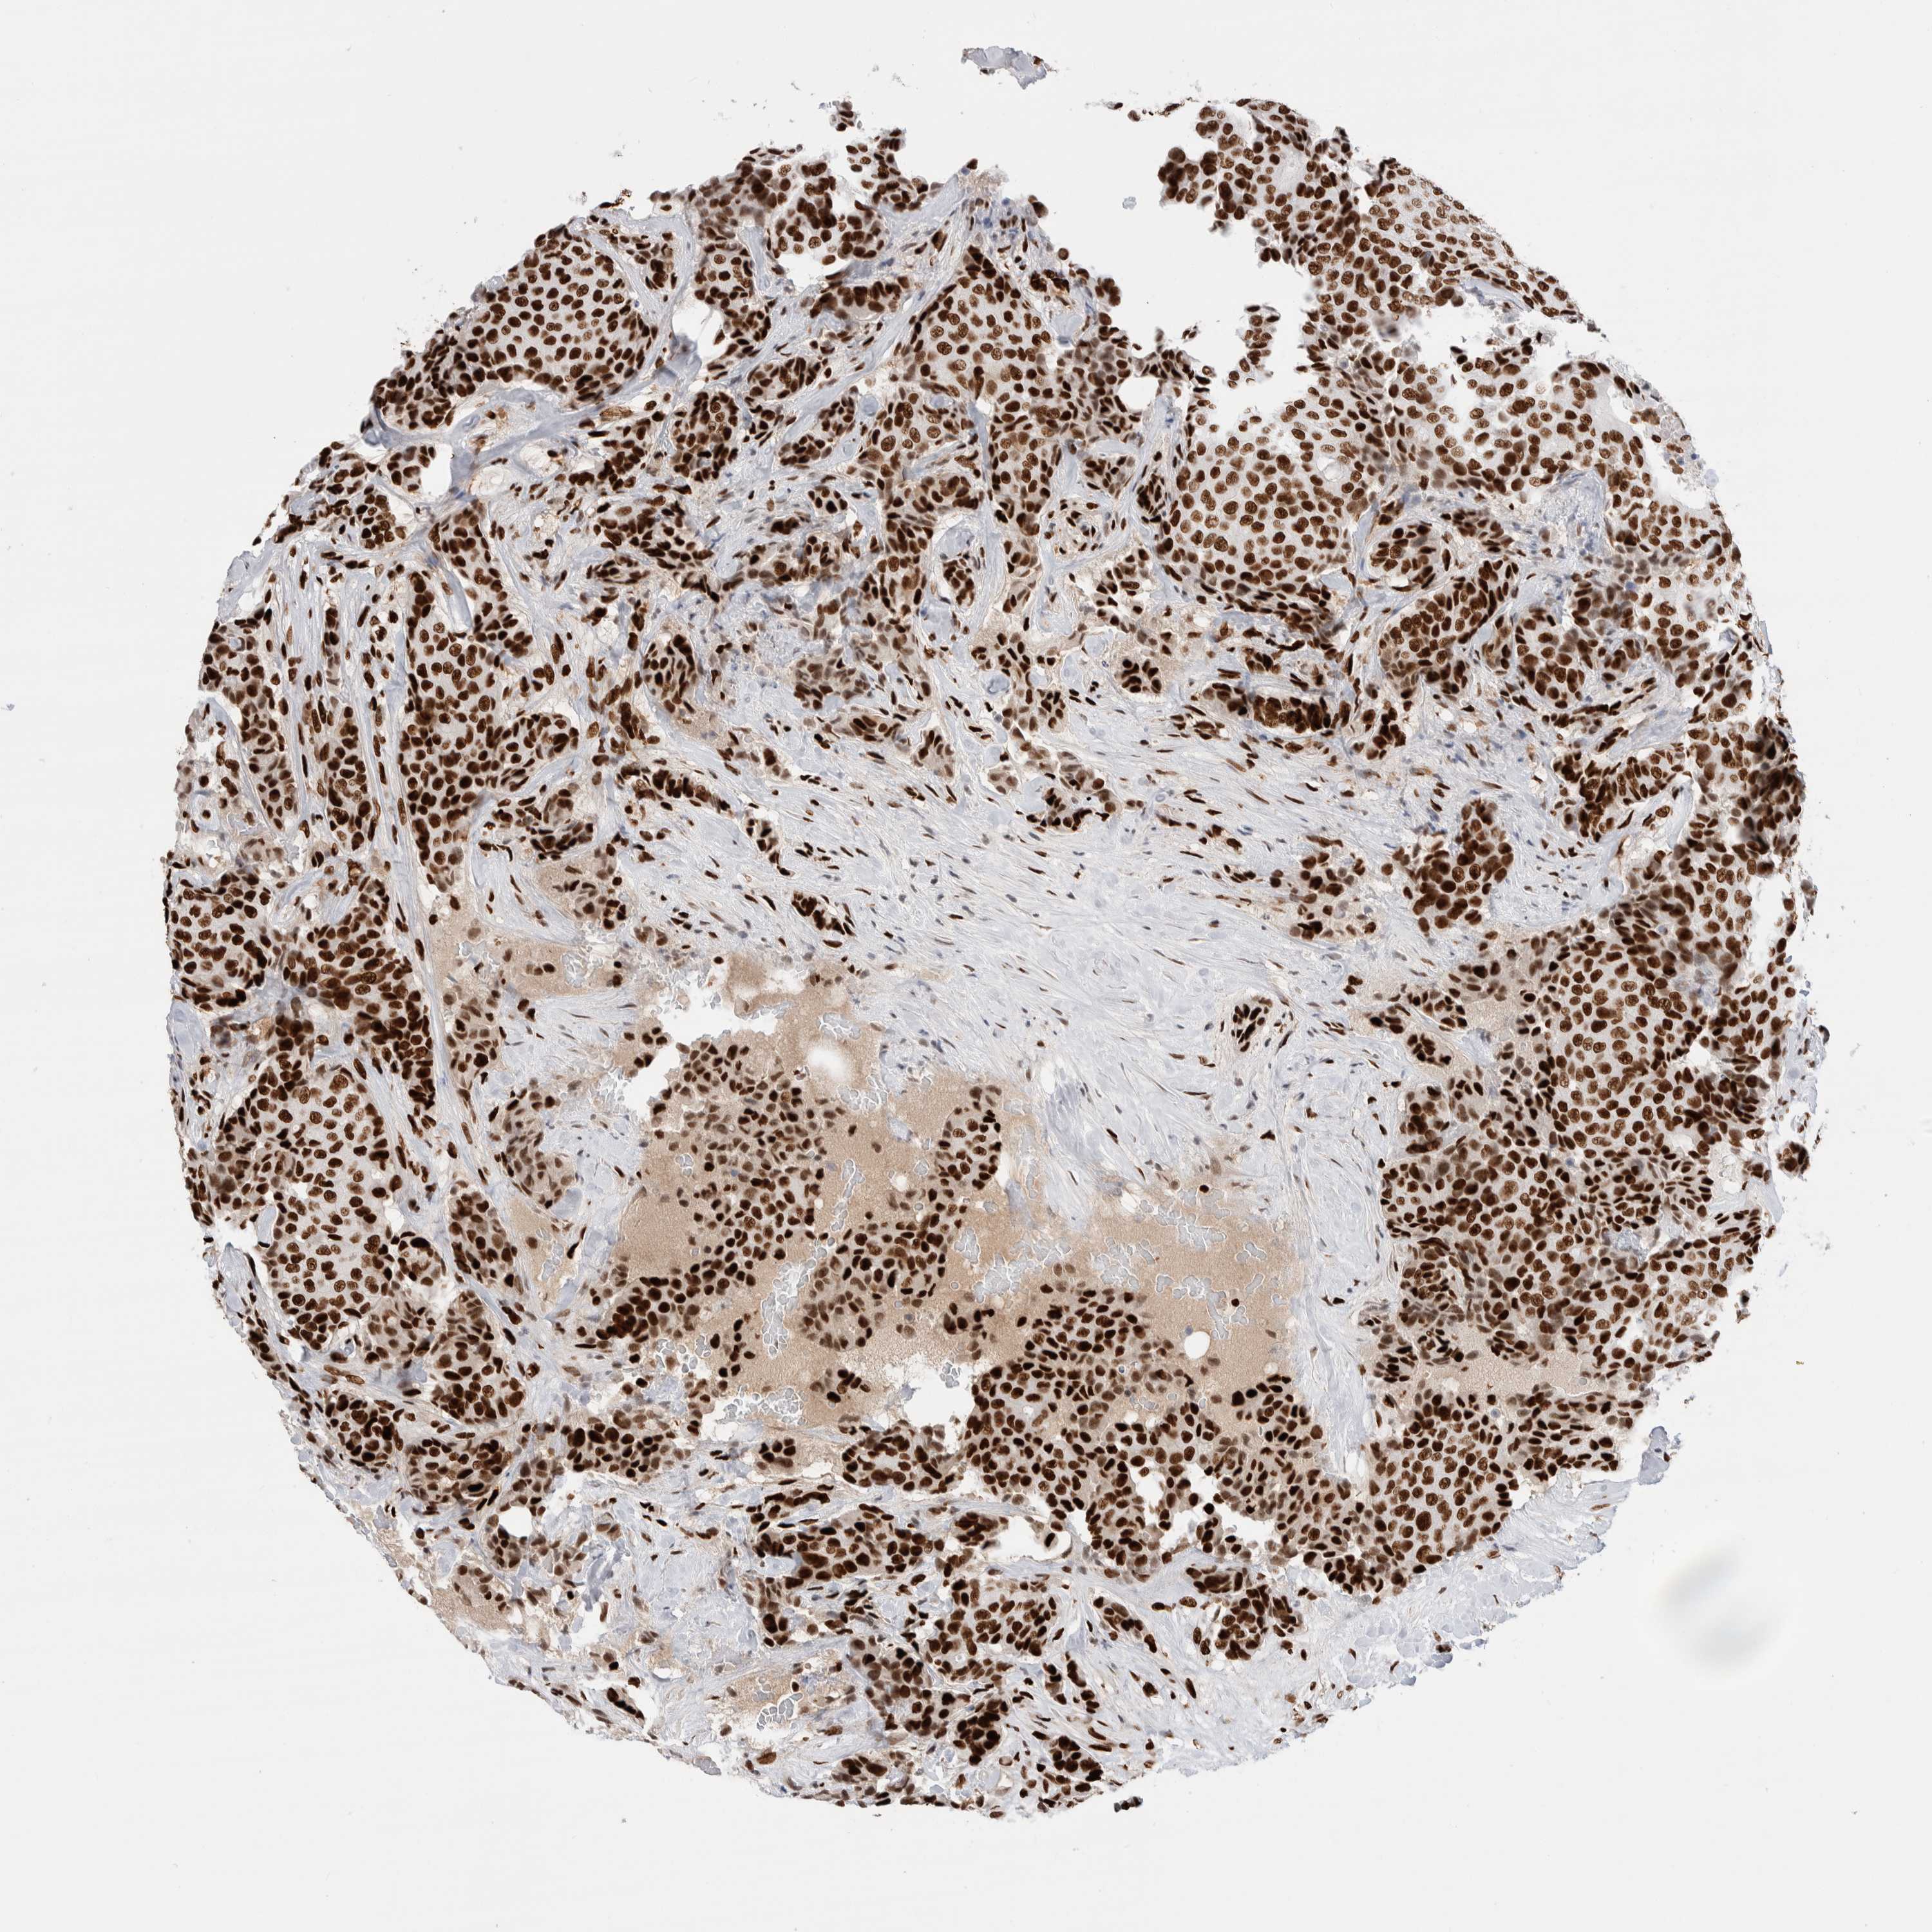

BRCA TCGA BRCA VALIDATION PROTEIN EXPRESSION